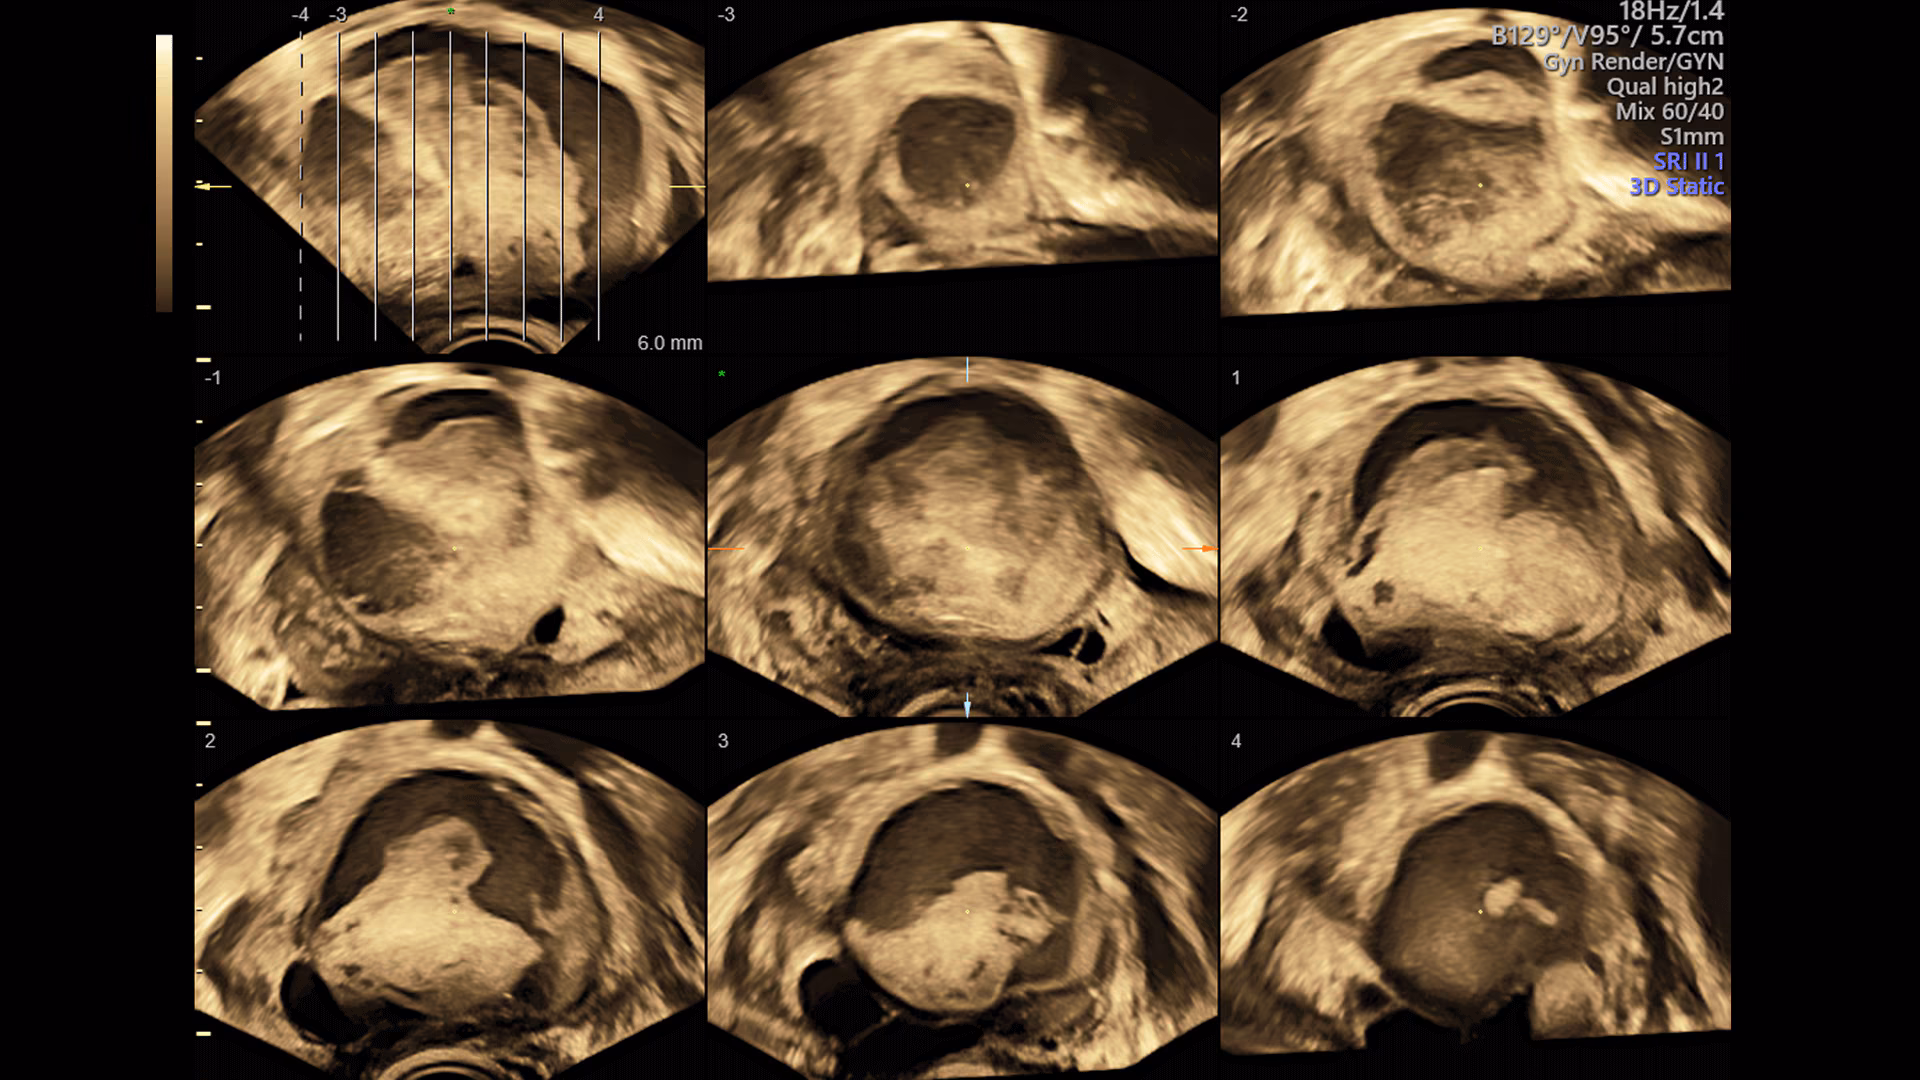

Sistema ecografico per ostetricia, ginecologia e fertilità

VOLUSON S8 con Touch panel

- 3D Uterine Trace

- Immagini veloci chiare e uniformi

- Dettaglio e risoluzione di contrasto eccezionale

- Visualizzazione dei piccoli vasi e dei bordi nel cuore fetale con RadiantFlowTM

- HDlive: tecnologia di rendering 3D/4D di Voluson che trasforma i dati ecografici in immagini più realistiche con profondità, illuminazione e texture migliorate